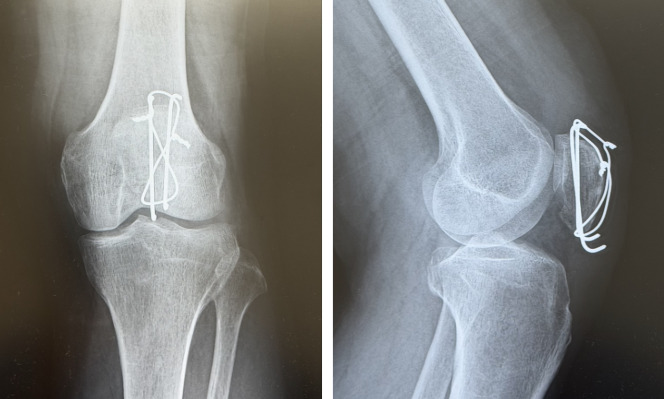

手術療法は、横骨折や粉砕骨折、あるいは関節面転位が大きい症例で選択されることが多く、テンションバンドワイヤリングやスクリュー固定などで内固定を行います。術後は膝関節の拘縮を防ぐため、固定の安定性を前提に早期から運動療法(可動域訓練)を進めます。手術は、特に下極骨片を確実に固定できるかが成績に影響しやすく、骨片の大きさや粉砕の程度を踏まえた固定戦略が重要です。なお、治療方針や固定性が確保できていることを前提に、術後すぐから荷重歩行を開始することもあります。